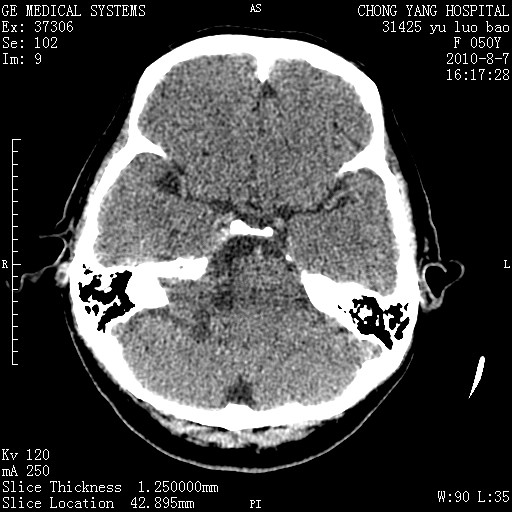

右侧桥小脑角区占位--听神经瘤,建议增强或mri检查。

右侧桥小脑角去等密度占位,右侧内听道扩大、骨质吸收,考虑:右侧听神经瘤,建议增强检查。

右侧内听道扩大、骨质吸收,中脑受压左移,考虑:右侧听神经瘤,建议增强检查。支持!

右侧桥小脑角区等密度占位,内耳道扩大,听神经瘤